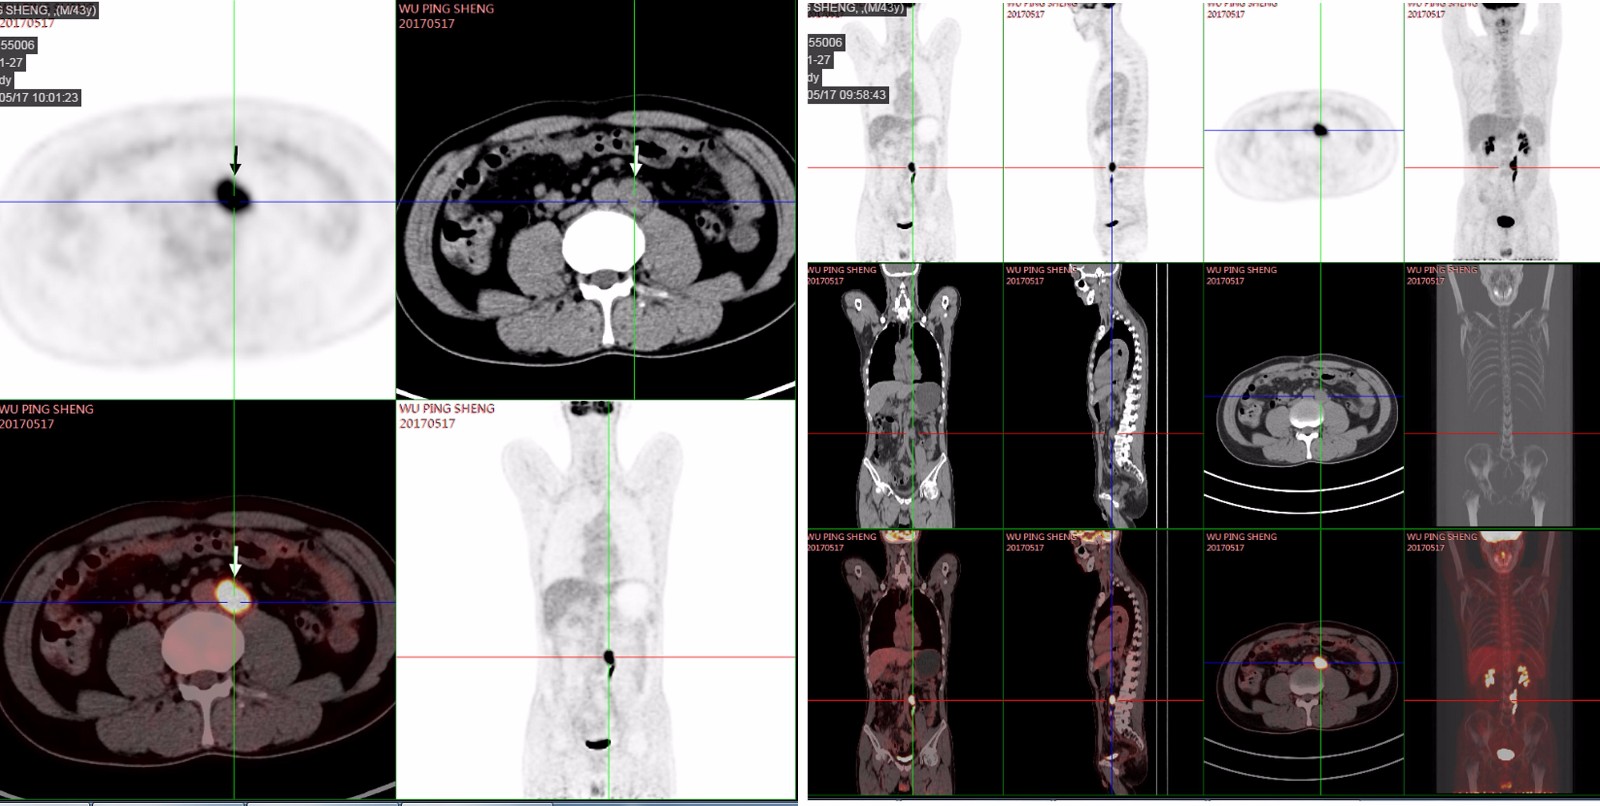

PET/CT:描述:L3水平腹膜后一枚肿大淋巴结,约2.3*1.7cm,放射性摄取异常增高,SUVmax=11.2。结论:1、直肠癌术后化疗后,腹膜后淋巴结转移,FDG高代谢。 2、胆囊结石;左肾结石。

2017.3.20 肿瘤抗原:CEA:6.89,AFP:1133.00。2017.3.20日起行XELOX方案化疗3次,末次化疗日期2017.5.3。期间2017.3.30腹部MR:腹膜后肿大淋巴结。2017.5.3 CEA: 14.59,AFP:2188。2017.5.12腹部MR:腹膜后肿大淋巴结,较前相仿。2017.5.17 PET/CT:直肠癌术后化疗后,腹膜后淋巴结转移,FDG高代谢;胆囊结石。